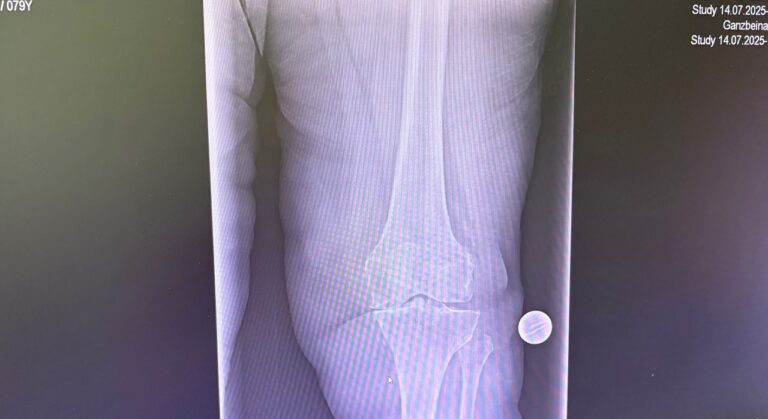

Πότε ενδείκνυται

- Προχωρημένη οστεοαρθρίτιδα γόνατος

- Παραμορφώσεις (ραιβό / βλαισό γόνατο)

- Ασθενείς με αυξημένες λειτουργικές απαιτήσεις

- Επανεπεμβάσεις ή δύσκολες ανατομίες